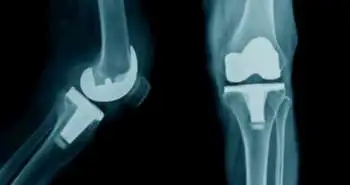

A total of 38 patients who took treatment in Cabueñes hospital and had two ipsilateral femoral implants, distal and proximal were selected for an observational, retrospective case-control analysis. Twenty-eight patients had no fracture and 10 cases found to have interimplant fracture. The impact of gender, age, radiological variables, and type of treatments, comorbidities and clinical evolution were also investigated.

The gender that met with most of the femoral fractures was females with 80.7 average age. Osteoporosis considered as a significant risk factor in the progression of these fractures. No statistical significance was seen with concern to the radiological variables. Most frequently used management approach was the surgery with the plate of osteosynthesis. The death rate at four years found to be of 40%. However, all fractures recovered, but the ambulation ability of survivors' was diminished. Particular therapeutic algorithms and classification methods are required to enhance the prognosis and management of these fractures.